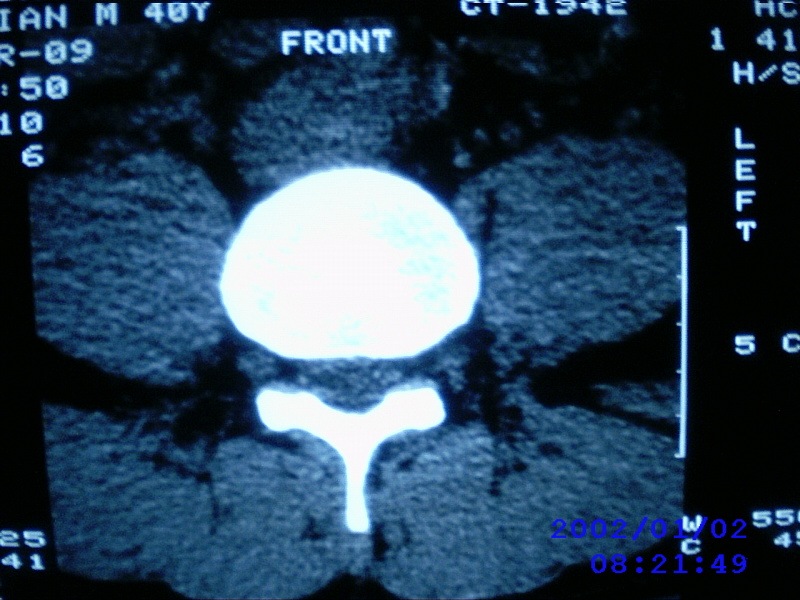

患者,男性,40岁,腰痛伴左下肢疼痛、麻木6年。5年前做过腰椎间盘手术,具体是哪个位置病人记不清了。

我拍的是l4-5、l5-s1

1)l4/5及l5/s1左侧椎板术后改变。2)l5/s1椎间盘突出,l5椎体下缘许莫氏结节。3)l4/5椎间盘膨出并突出。4)l3/4椎间盘膨出。

1)l4/5及l5/s1左侧椎板术后改变。2)l5/s1椎间盘突出,l5椎体下缘许莫氏结节。3)l4/5椎间盘膨出并突出。